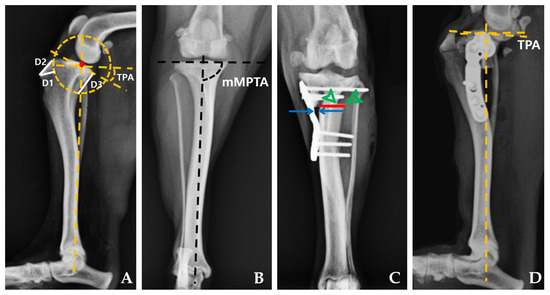

2.4.1. Radiographic Measurements

| Preoperative TPA (°) | 25.00 | 2.00 | 25.25 | 2.86 | 0.798 |

| Postoperative TPA (°) | 5.48 | 1.66 | 5.38 | 2.15 | 0.878 |

| Preoperative mMPTA (°) | 96.96 | 4.33 | 96.13 | 6.17 | 0.721 |

| Postoperative mMPTA (°) | 97.04 | 1.84 | 94.34 | 4.38 | 0.131 |

| Bone–plate gap (mm) | 0.59 | 0.54 | 1.90 | 0.44 | 0.001 |